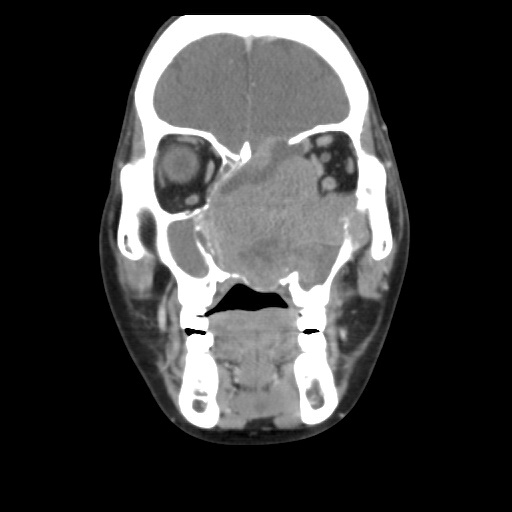

圖說:53歲的板太太確診鼻竇癌,腫瘤持續增生造成顏面變形

「在寮國即使生病想看醫生得翻山越嶺,經濟上也負擔不起,病了好幾個月,忍耐已經成了一種習慣。」2019年5月,板太太臉上的腫瘤大到甚至影響到呼吸,才在當地醫院檢查,被診斷是罹患了鼻竇癌,並接受內視鏡手術,取出部分腫瘤。板太太說,沒想到手術後才短短三個月的時間,腫瘤增生的很快速,不僅堵住鼻腔,且巨大腫瘤甚至侵蝕了鼻中膈,導致對側鼻腔空間也受到擠壓,造成雙側鼻塞,鼻孔不時化膿、流出血水,散發出難聞的味道,不只影響到呼吸功能,就連左眼視力也逐漸變得模糊,頭也會不時感覺脹痛,真的相當辛苦。「鼻竇癌是比較少見的一種頭頸癌,在頭頸癌之中比率不到百分之五。」板太太的主治醫師耳鼻喉科陳培榕副院長表示,病理切片檢查結果發現,這是組織細胞型態較罕見的神經內分泌癌,腫瘤大小約七*八*六公分,不僅位置非常深且涵蓋範圍很大,包括腦部顱底、腦膜、雙側鼻腔、左上頜竇及左眼窩內側等重要部位,且顱底的腫瘤有持續向上生長近入顱內壓迫腦部的狀況,外觀也因腫瘤將眼睛和鼻子擠壓變形。

圖說:板太太歷經一個半月、三次的引導式化療起先腫瘤壓迫顱底、鼻腔和眼睛的狀況,在化療後都獲得控制,甚至明顯縮小至約五公分

經過陳培榕副院長與血液腫瘤科王佐輔主任討論後決定先進行引導式化療,先把腫瘤縮小,進而能達到開刀及輔助性的放射治療。陳培榕副院長表示,板太太在第一次引導式化療後,腫瘤明顯小了很多,讓醫療團隊更有信心。歷經一個半月、三次的引導式化療,幸好並沒有出現嚴重的化療副作用,起先腫瘤壓迫顱底、鼻腔和眼睛的狀況,在化療後都獲得控制,甚至明顯縮小至約五公分。2020年1月22日,耳鼻喉科團隊由陳培榕副院長與楊妙君醫師聯手,俐落的刀法,細細避開重要血管,且以新技術克服出血問題。陳副院長說:「外頸動脈是將血流帶到顏面及鼻子的主要血管,為了避免術中的出血量過多,所以使用『血管帶』束縛外頸動脈這種新技術,不把外頸動脈綁死、只是束緊一點,出血量可以減少約500到700c.c,提升手術的視野,看得清楚腫瘤的邊緣能將腫瘤切得愈乾淨。」陳培榕副院長表示,近十幾年來,花蓮慈院大約完成近十例的顏面巨大腫瘤個案,其中包含馬來西亞的惡性腫瘤「皮膚纖維肉瘤」患者與菲律賓的「牙骨質纖維瘤」患者都是使用這項新技術,無論是腫瘤移除與顏面重建整形,患者的預後都相當好。